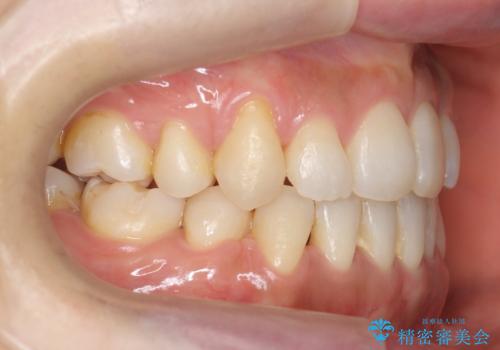

八重歯 上下の正中のずれ 40代で抜歯矯正

- 八重歯と上下の正中のずれを気にして来院。

上の前歯の正中が右にずれていました。

小臼歯抜歯を行い、ワイヤー矯正を行いました。

時間はかかりましたがしっかり治療することができました。